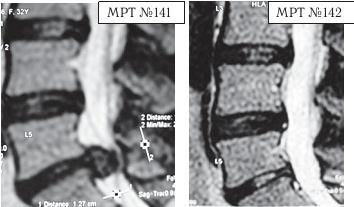

На МРТ № 139 — состояние поясничного отдела позвоночника: рецидив грыжи межпозвонкового диска после хирургической операции. Наблюдается абсолютный стеноз спинномозгового канала, грыжа межпозвонкового диска в сегменте LV-SI , осложнённая массивным секвестром с его миграцией как в каудальном (вниз), так и в краниальном (вверх) направлении. Размер грыжи дорсально — до 14,5 мм, каудально-краниально — до 26,8 мм. На МРТ № 140 наблюдается состояние поясничного отдела позвоночника после лечения методом вертеброревитологии: отсутствие грыжи межпозвонкового диска в сегменте LV-SI , отсутствие стеноза позвоночного канала. А вот этот случай запомнился упорством пациента, страх которого перед операцией был столь велик, несмотря на значительные боли, что по сути сами нейрохирурги, уставшие объяснять ему очевидные вещи и знавшие не понаслышке о методе вертеброревитологии, «переадресовали» строптивого пациента ко мне в клинику. Но, как говорится, всё, что ни делается, — всё к лучшему. ![]() На МРТ № 141 наблюдается состояние поясничного отдела позвоночника: секвестрированная грыжа межпозвонкового диска в сегменте LV-SI, абсолютный стеноз спинномозгового канала. На МРТ №°142 — состояние поясничного отдела позвоночника данного пациента после лечения методом вертеброревитологии: отсутствует грыжа межпозвонкового диска в сегменте LV-SI, более того, наблюдается активизация репаративного процесса в межпозвонковом диске данного сегмента. Состояние данного пациента было тяжёлым, в течение двух месяцев боли не купировались и он практически не спал. Нейрохирурги настаивали на срочной операции и были правы: показания к операции в данном случае — 100 %. Но пациент испытывал сильное беспокойство и страх по этому поводу, так как после аналогичной операции его родственник утратил способность к самостоятельному передвижению, стал инвалидом и потерял доходную работу. Ну что поделаешь, если человек был свидетелем таких печальных последствий, как говорится в пословице, — только слепой не боится призраков. Как врачи ни объясняли сложность его ситуации, пациент упорно не хотел оперироваться, а лекарства уже практически не действовали. Но нейрохирурги ведь тоже люди, терпение у них хоть и большое, но не «железное». В результате они дали пациенту адрес клиники вертеброревитологии. Как оказалось впоследствии, эта попытка нейрохирургов помочь пациенту была поистине их «соломоновым решением». Бывали случаи, когда пациенты с большими секвестрированными грыжами проходили всего лишь один курс лечения (24 сеанса), после которого наблюдалось не только устранение грыж, но и происходило довольно быстрое восстановление как межпозвонковых дисков, так и биомеханики позвоночника. Какие обстоятельства этому способствовали? Помимо построения биомеханической конструкции методом вертеброревитологии, этому также способствовали индивидуальные особенности данных пациентов (приемлемые для регенерации возрастные характеристики пациента (до 60 лет), отсутствие лишнего веса, наличие хорошего иммунитета и много других предрасполагающих к данному лечению факторов), соблюдение пациентами элементарных условий для реабилитации (восстановления) позвоночника. Такие случаи, где было достаточно одного курса методом вертеброревитологии, конечно, единичны. Однако они весьма показательны по вариабельности возможностей мобилизации и восстановления человеческого организма. Вот один из таких случаев. Он связан с моим пациентом — известным певцом, телеведущим да и просто хорошим человеком. Как в этом случае, так и в дальнейшем по этическим соображениям я не буду называть фамилии данных людей, а буду опираться лишь на конкретные результаты.